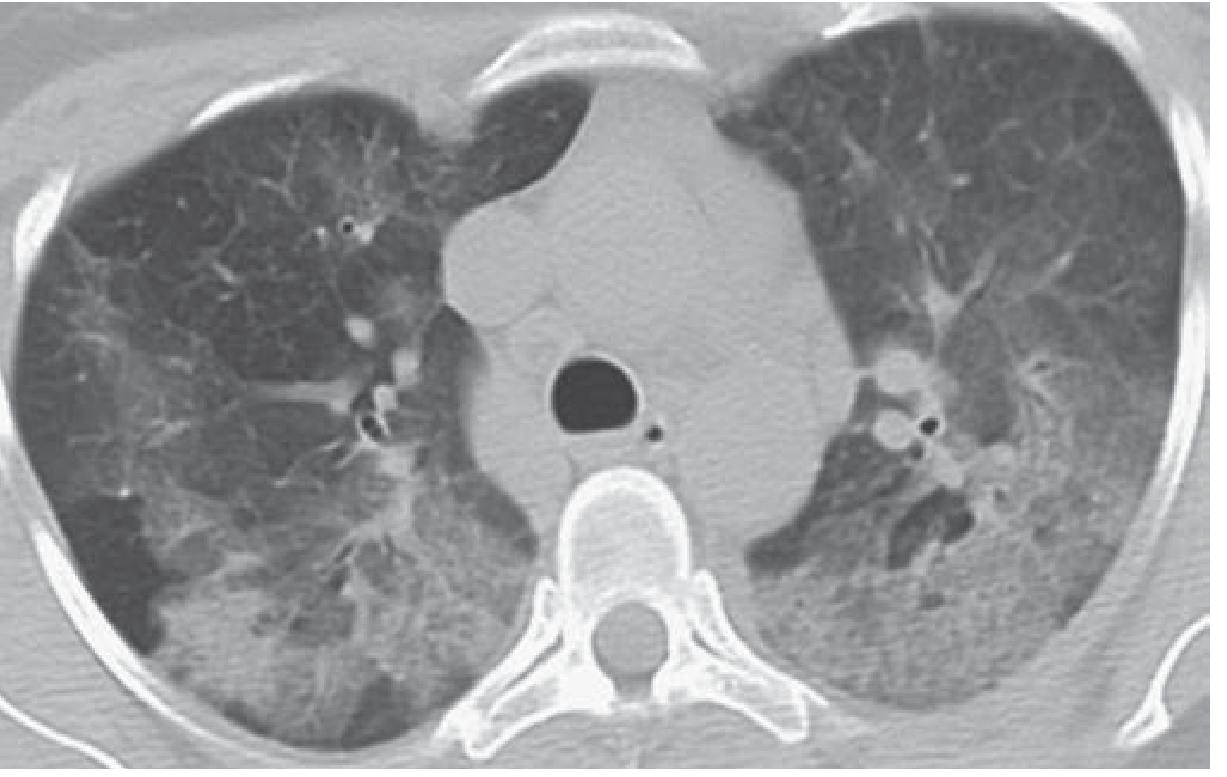

CT chest in AEP showing bilateral diffuse ground-glass opacity and consolidation

Diffuse bilateral ground-glass opacity and consolidation in AEP — Fishman's Pulmonary Diseases and Disorders

• Bilateral ground-glass opacification and consolidation in a random (non-segmental) distribution

• Interlobular septal thickening

• Thickening of bronchovascular bundles

• Small to moderate bilateral pleural effusions

• Mediastinal lymphadenopathy (common)

• CT appearance can mimic pulmonary edema or DAD